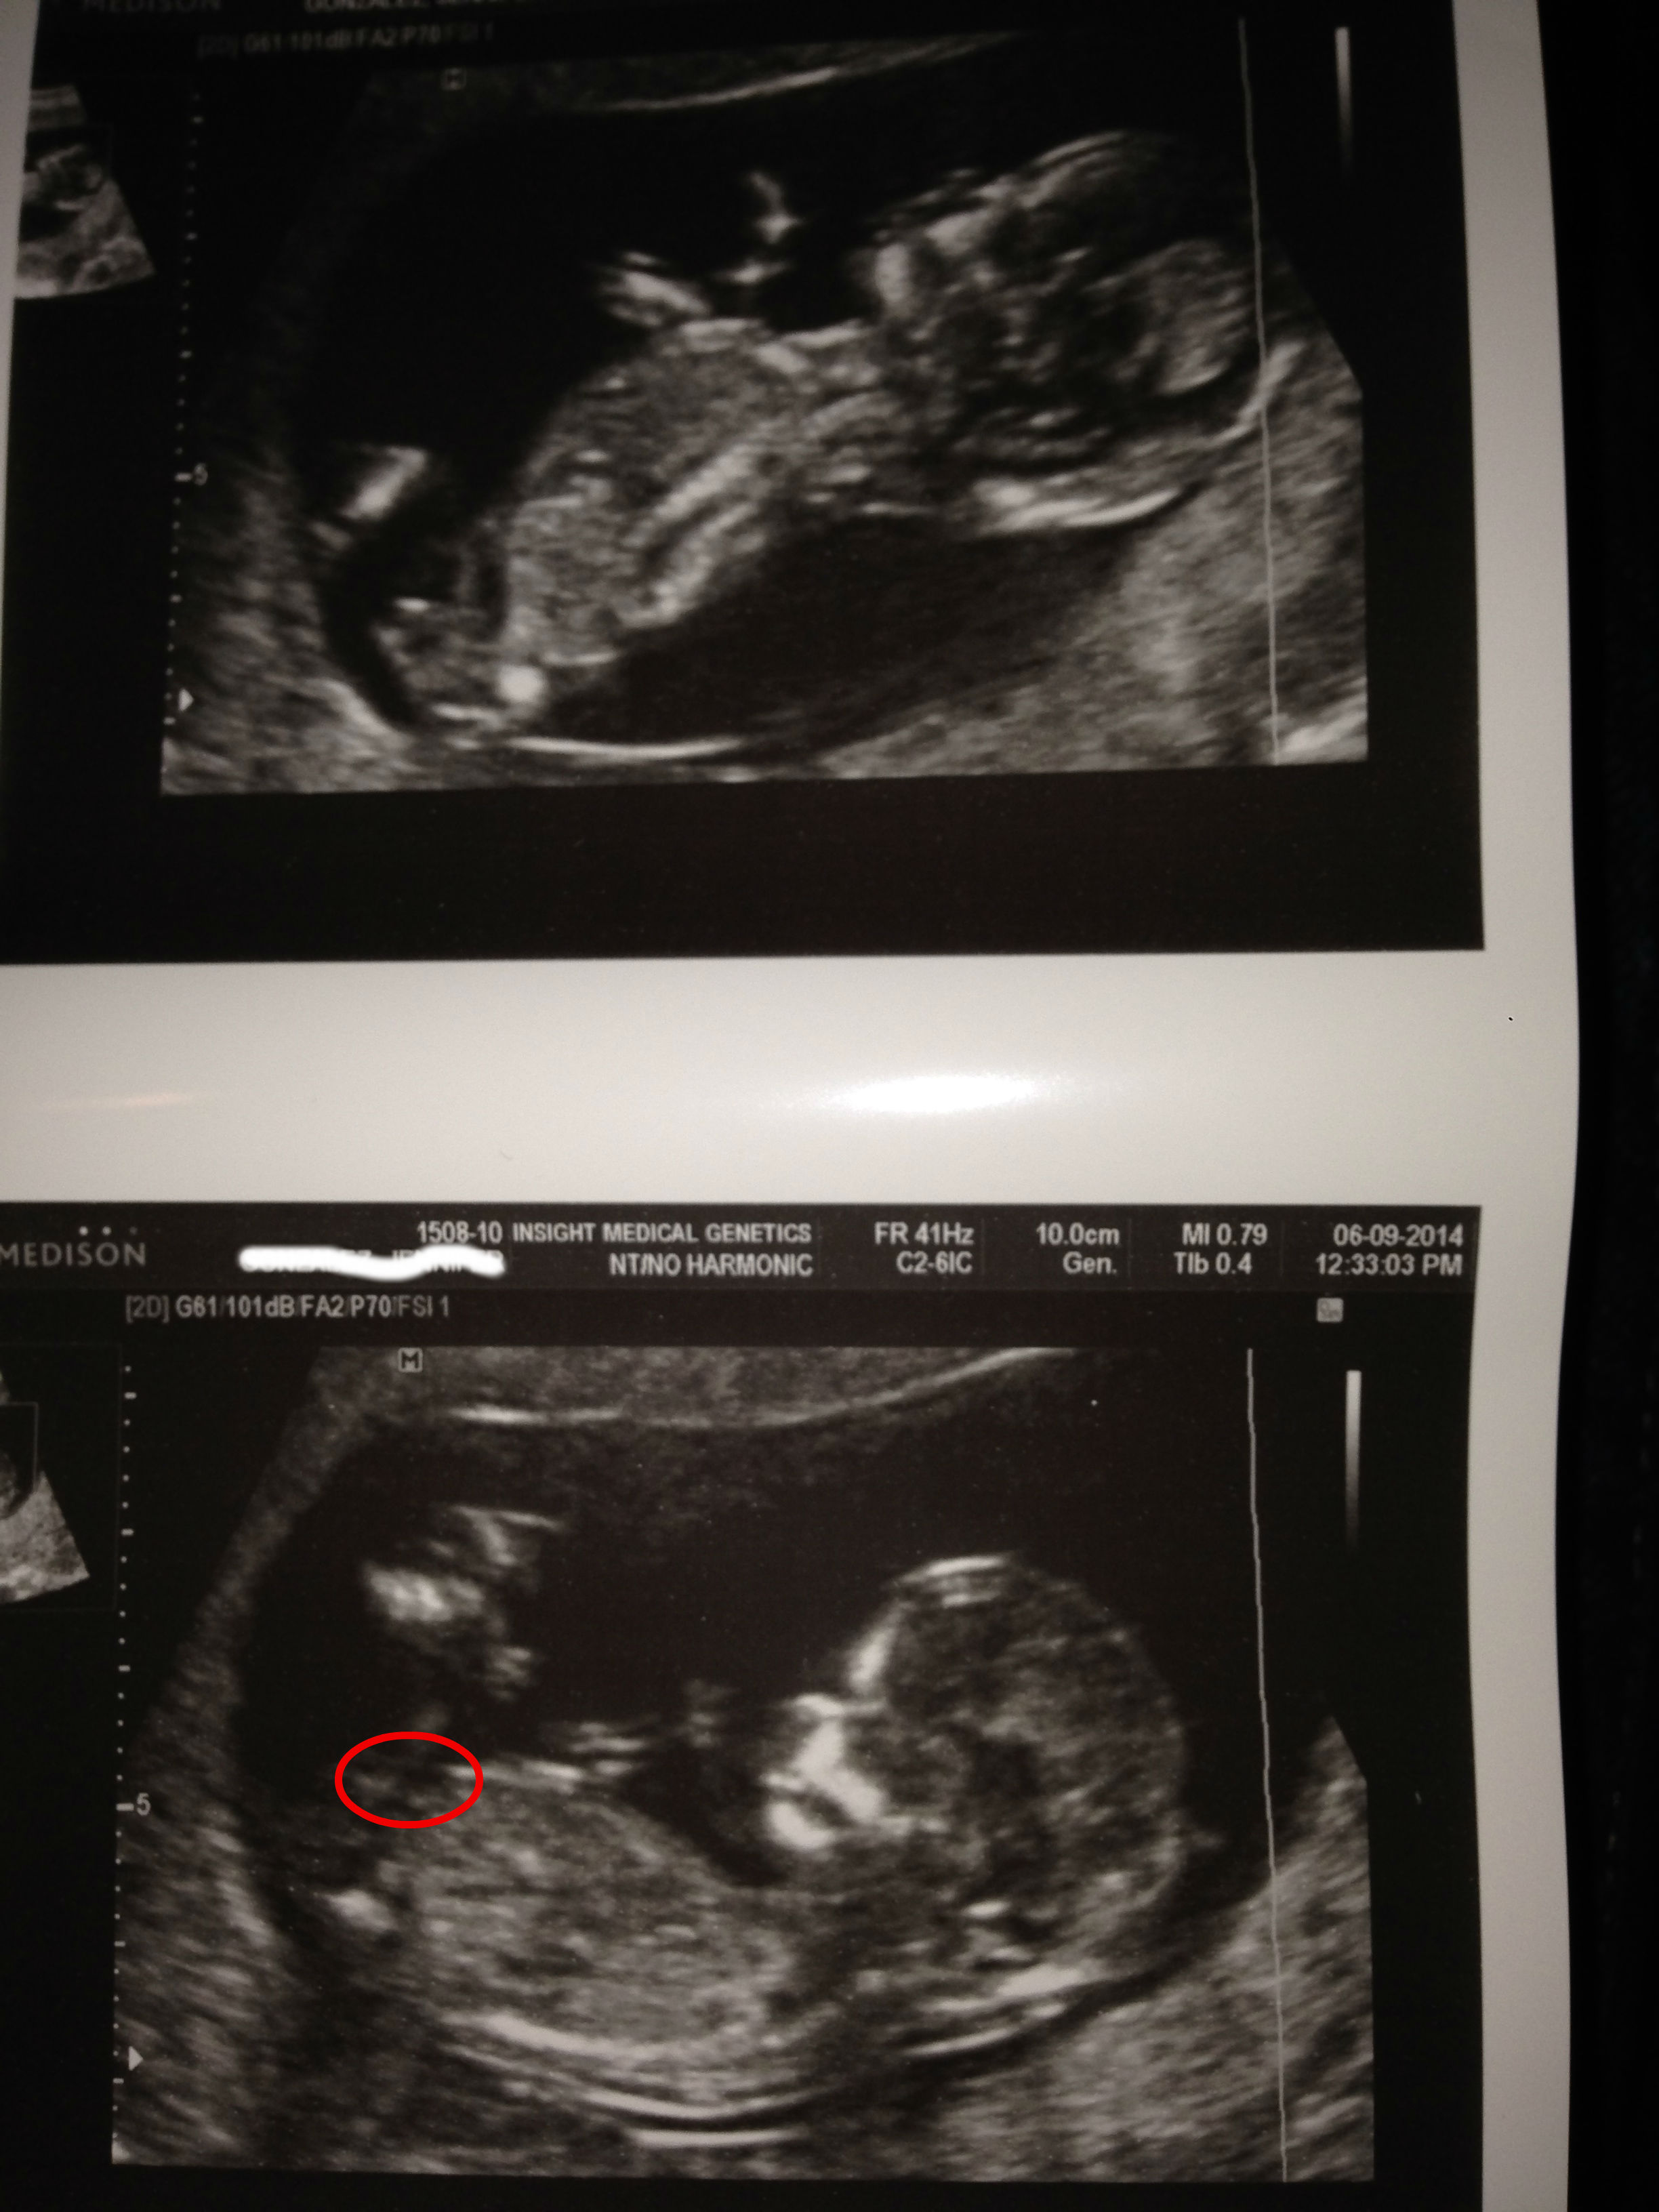

I was told there wasnt a nub in any of my pics and i am generally not good at spotting them anyway but on my son's the nub was roughly where i notated in this attached picture. And i think i see a line there- but that isnt the nub's location?Attachment 19361

No, I think that is still the belly. I think there's maybe a nub in the top pic that looks boyish but I wouldn't trust it since baby seems to be very active and not laying flat.

I think that's too high up to be the nub where you circled.

It may be and may not be. The problem is that it's too dark and if it is the nub I don't think the whole nub is shown.

whatever it is, it's not a good nub because in the one, the baby's back is arched and in the other, they are curled up tight. no reliable cues from either pic